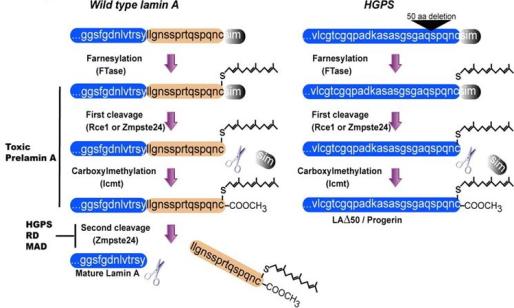

A lâmina A é sintetizada por uma molécula precursora, denominada prelamina A, em quatro etapas pós-tradução. Todas as prelaminas apresentam um domínio globular na sua extremidade C-terminal e outro na N-terminal. O terminal carboxílico contém um motivo característico CAAX (C é cisteína, A é um aminoácido alifático e X é o aminoácido terminal) que é modificado por farnesilação, ou seja, uma feniltransferase adiciona um grupo farnesil (isoprenóide de 15 carbonos) em proteínas que possuem a cisteína no terminal carboxilo.

Posteriormente ocorre uma libertação endoproteolítica dos três últimos aminoácidos da proteína, seguida de metilação do terminal carboxílico farnesil-cisteína por uma metiltransferase. Por último ocorre a libertação endoproteolítica dos últimos quinze aminoácidos havendo libertação da lâmina A. Este esquema de processamento é crucial para a adesão da lâmina A ao invólucro nuclear.

A mutação mais frequente no gene LMNA, em casos de progeria, é originada pela substituição de um nucleótido na posição 1824, de citosina para timina, esta mutação não origina troca de aminoácido, mas ativa um sítio de splicing críptico (áreas alternativas ao splicing que competem com as áreas normais) que provoca a deleção de 50 aminoácidos do terminal carboxílico (Figura 1).

Figura 1 – Representação esquemática da síntese de lâmina A e de progerina, prelamina A mutada, responsável pelo desenvolvimento da progeria.

Na progeria o sítio de reconhecimento da enzima que requer a clivagem da prelamina A a lâmina A está mutado, não ocorrendo clivagem do grupo farnesil, formando assim uma proteína anormal denominada de progerina, uma forma truncada da prelamina A. A progerina é tóxica para a célula, acumula-se nas células causando defeitos moleculares progressivos, incluindo alterações do formato nuclear, desorganização da cromatina, danos no DNA e atraso na proliferação celular (Figura 2).